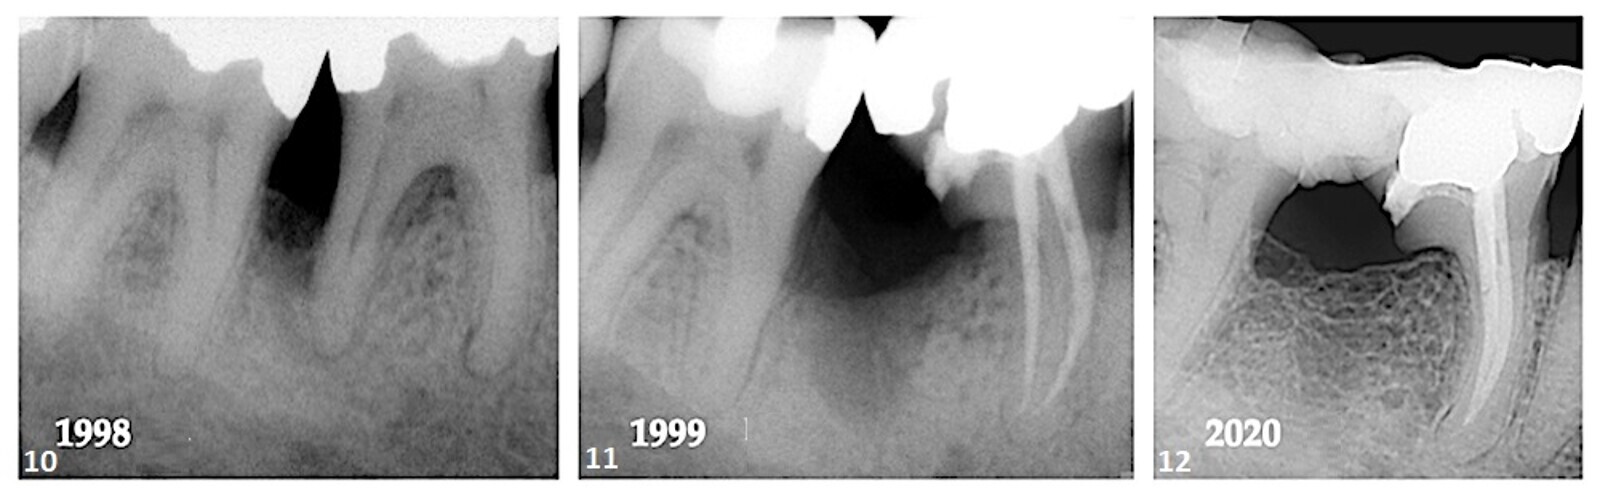

En octobre 1998, un homme de 39 ans s'est présenté au cabinet en se plaignant d'une sensibilité gingivale dans le quadrant mandibulaire droit. Une perte osseuse importante a été notée interproximalement entre la dent #47 et la dent #46 ; cependant, l'état parodontal de la dentition en général était dans les limites normales. Les tests de sensibilité pulpaire des dents dans le quadrant mandibulaire droit ont identifié la pulpe de la dent n° 46 comme étant nécrotique (Fig. 10). Il a été expliqué au patient que le traitement des lésions parodontales et endodontiques était en général défavorable et que le succès dépendait de la sévérité de la perte osseuse, de la longueur du tronc radiculaire, du degré de séparation radiculaire, de la courbure de la racine à réséquer, de la capacité à éradiquer la défaut, l'état pulpaire et les procédures de restauration et d'hygiène buccale requises.

Avec le consentement du patient, la racine distale de la dent n° 46 a été réséquée et la couronne sus-jacente a été conservée (Fig. 11). À un moment donné après la procédure d'amputation, le dentiste référent a attelé les dents n° 47 et 46 avec un pont en composite et en ruban. Vingt-deux ans après la procédure initiale, la régénération osseuse et la cortication dans la région furcale étaient évidentes entre les dents #47 et 46 (Fig. 12).

Cas 2—fig. 10 : La perte osseuse entre la dent #47 et la dent #46 et la perte du ligament parodontal autour de la région apicale des racines mésiales et distales étaient évidentes. Fig. 11 : Après résection de la racine distale, le degré de perte osseuse semble avoir augmenté. Fig. 12 : Un suivi de 22 ans a montré une régénération de l'os interproximal perdu et une cortication de la crête alvéolaire.